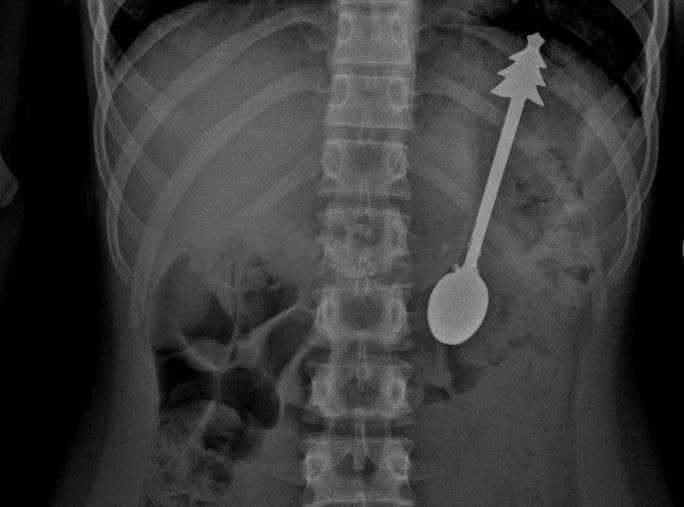

Ребенок случайно проглотил 14-сантиметровую ложку в Оренбурге.

Его срочно доставили в больницу, где провели операцию по удалению столового прибора с елочкой на ручке. Все прошло успешно, и уже на следующий день ребенка отпустили домой, сообщили в местном минздраве.